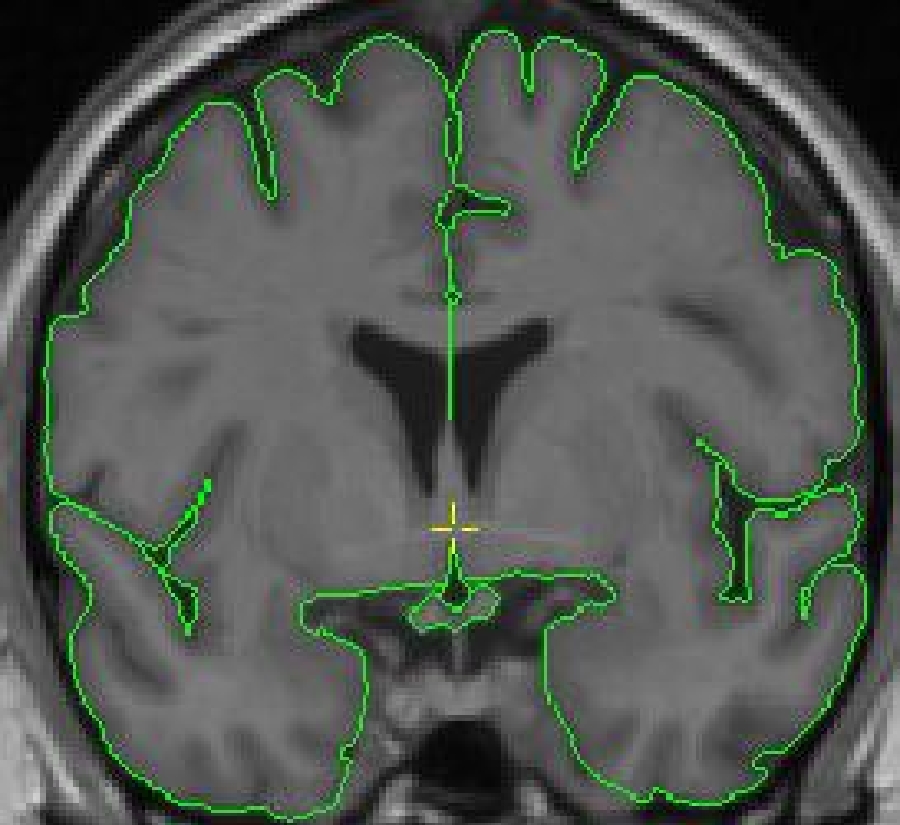

The outline for the optic chiasm is created using the intensity contour function ( press c) and manual drawing. Start segmenting the optic chiasm, from anterior to posterior, on the first slice it becomes the inferior border of the third ventricle. This is in the proximity of the coronal slice containing the anterior commissure.